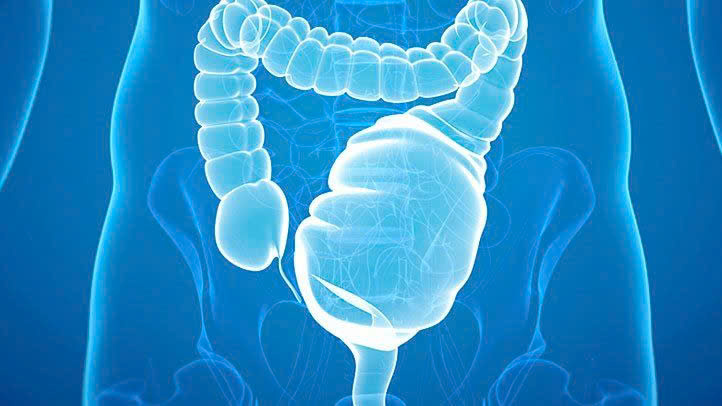

Táo bón lâu ngày dẫn đến ứ phân

Ứ phân là một chứng minh nghiêm trọng của táo bón kéo dài. Khi cơ thể không thể tống phân ra ngoài khiến nó ngày càng tích tụ nhiều trong ruột, dính vào nhau tạo thành khối tắc nghẽn lớn. Điều này làm ruột mất khả năng co bóp, không thể đưa phân ra ngoài, đặc biệt khi khối phân trở nên quá cứng và lớn.

Ứ phân nguy hiểm như thế nào?

Ứ phân được coi là một tình trạng cấp cứu y tế , gây ra hàng loạt chứng khó chịu và nguy hiểm như: